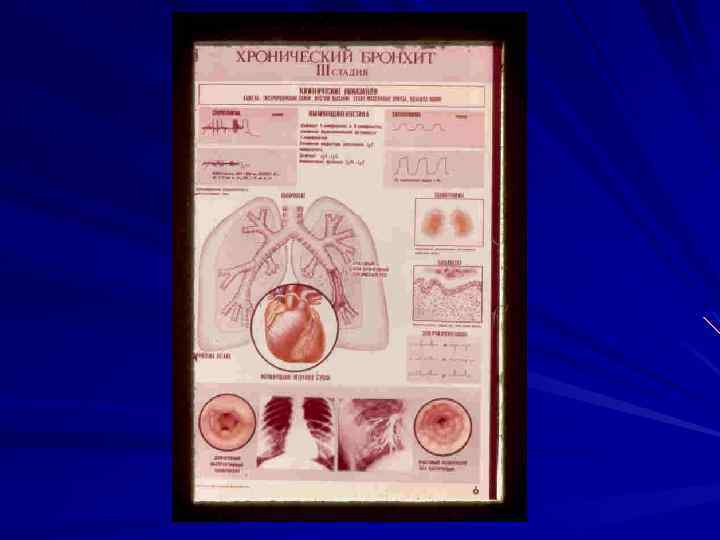

Морфология хронического бронхита: - увеличение в 1, 5 раза толщины стенок бронхов; - гипертрофия бронхиальных слизистых желез и бокаловидных клеток; - участки воспаления, склероза, дистрофических и атрофических изменений всех стенок бронхов (панбронхит); - гнойное пропитывание стенки бронхов с участками изъязвления (возможность кровотечения). - пневмофиброз, эмфизема легких. - развитие бронхоэктазов.

Классификация хронического бронхита. 1. По патогенезу: - первичный - вторичный 2. По клиническому течению: - «сухой» - катаральный - гнойный 3. По клинико-функциональной характеристике: - необструктивный - обструктивный

Продолжение. 4. По фазе болезни: - обострение; - ремиссия; 5. По осложнениям: - хронический обструктивный бронхит с эмфиземой (ХОБЛ); - легочная гипертензия, легочное сердце; - легочная (дыхательная) и сердечная ( по правожелудочковому типу) недостаточность.

Клиническое течение: - кашель, мокрота; - гипотоническая трахеобронхиальная дискинезия; - одышка (бронхоспастический и обструктивный синдром, степени дыхательной недостаточности). - цианоз диффузный, акроцианоз. - гиперкапния.

Продолжение. - Данные осмотра, перкуссии, аускультации (бочкообразная грудная клетка, коробочный тон, жесткое или ослабленное везикулярное дыхание, удлинен выдох, сухие хрипы). - Признаки обструкции (одышка при физической нагрузке, малопродуктивный кашель, удлиненный выдох, свистящие хрипы на выдохе, эмфизема легких, снижение показателей функции внешнего дыхания).

Диагностика хронического бронхита. - Кровь (эритроцитоз, увеличение гематокрита и вязкости крови, при обострении: лейкоцитоз, нейтрофиллез, СОЭ. - Мокрота (нейтрофильный лейкоцитоз, клетки бронхиального эпителия, эритроциты, макрофаги, нарушение реологических свойств). - Рентгенограмма грудной клетки (пневмофиброз, эмфизема легких, низкое стояние диафрагмы и снижение ее экскурсии). - Бронхография (выявление бронхоэктазов). - Бронхоскопия (исследование слизистой бронхов, производство биопсии).

-Функция внешнего дыхания (нормативы): ЖЕЛ: муж. – 4 – 5 л. Жен. – 3 – 4 л. ОФВ 1: муж. – 3 – 4 л. Жен. – 2 – 3 л. Индекс Тиффно: ОФВ 1/ЖЕЛ х 100 (70 – 85%). МВЛ: муж. – 100 – 125 л мин. жен. - 80 – 100 л мин. - Сканирование легких (радиоизотопное исследование).